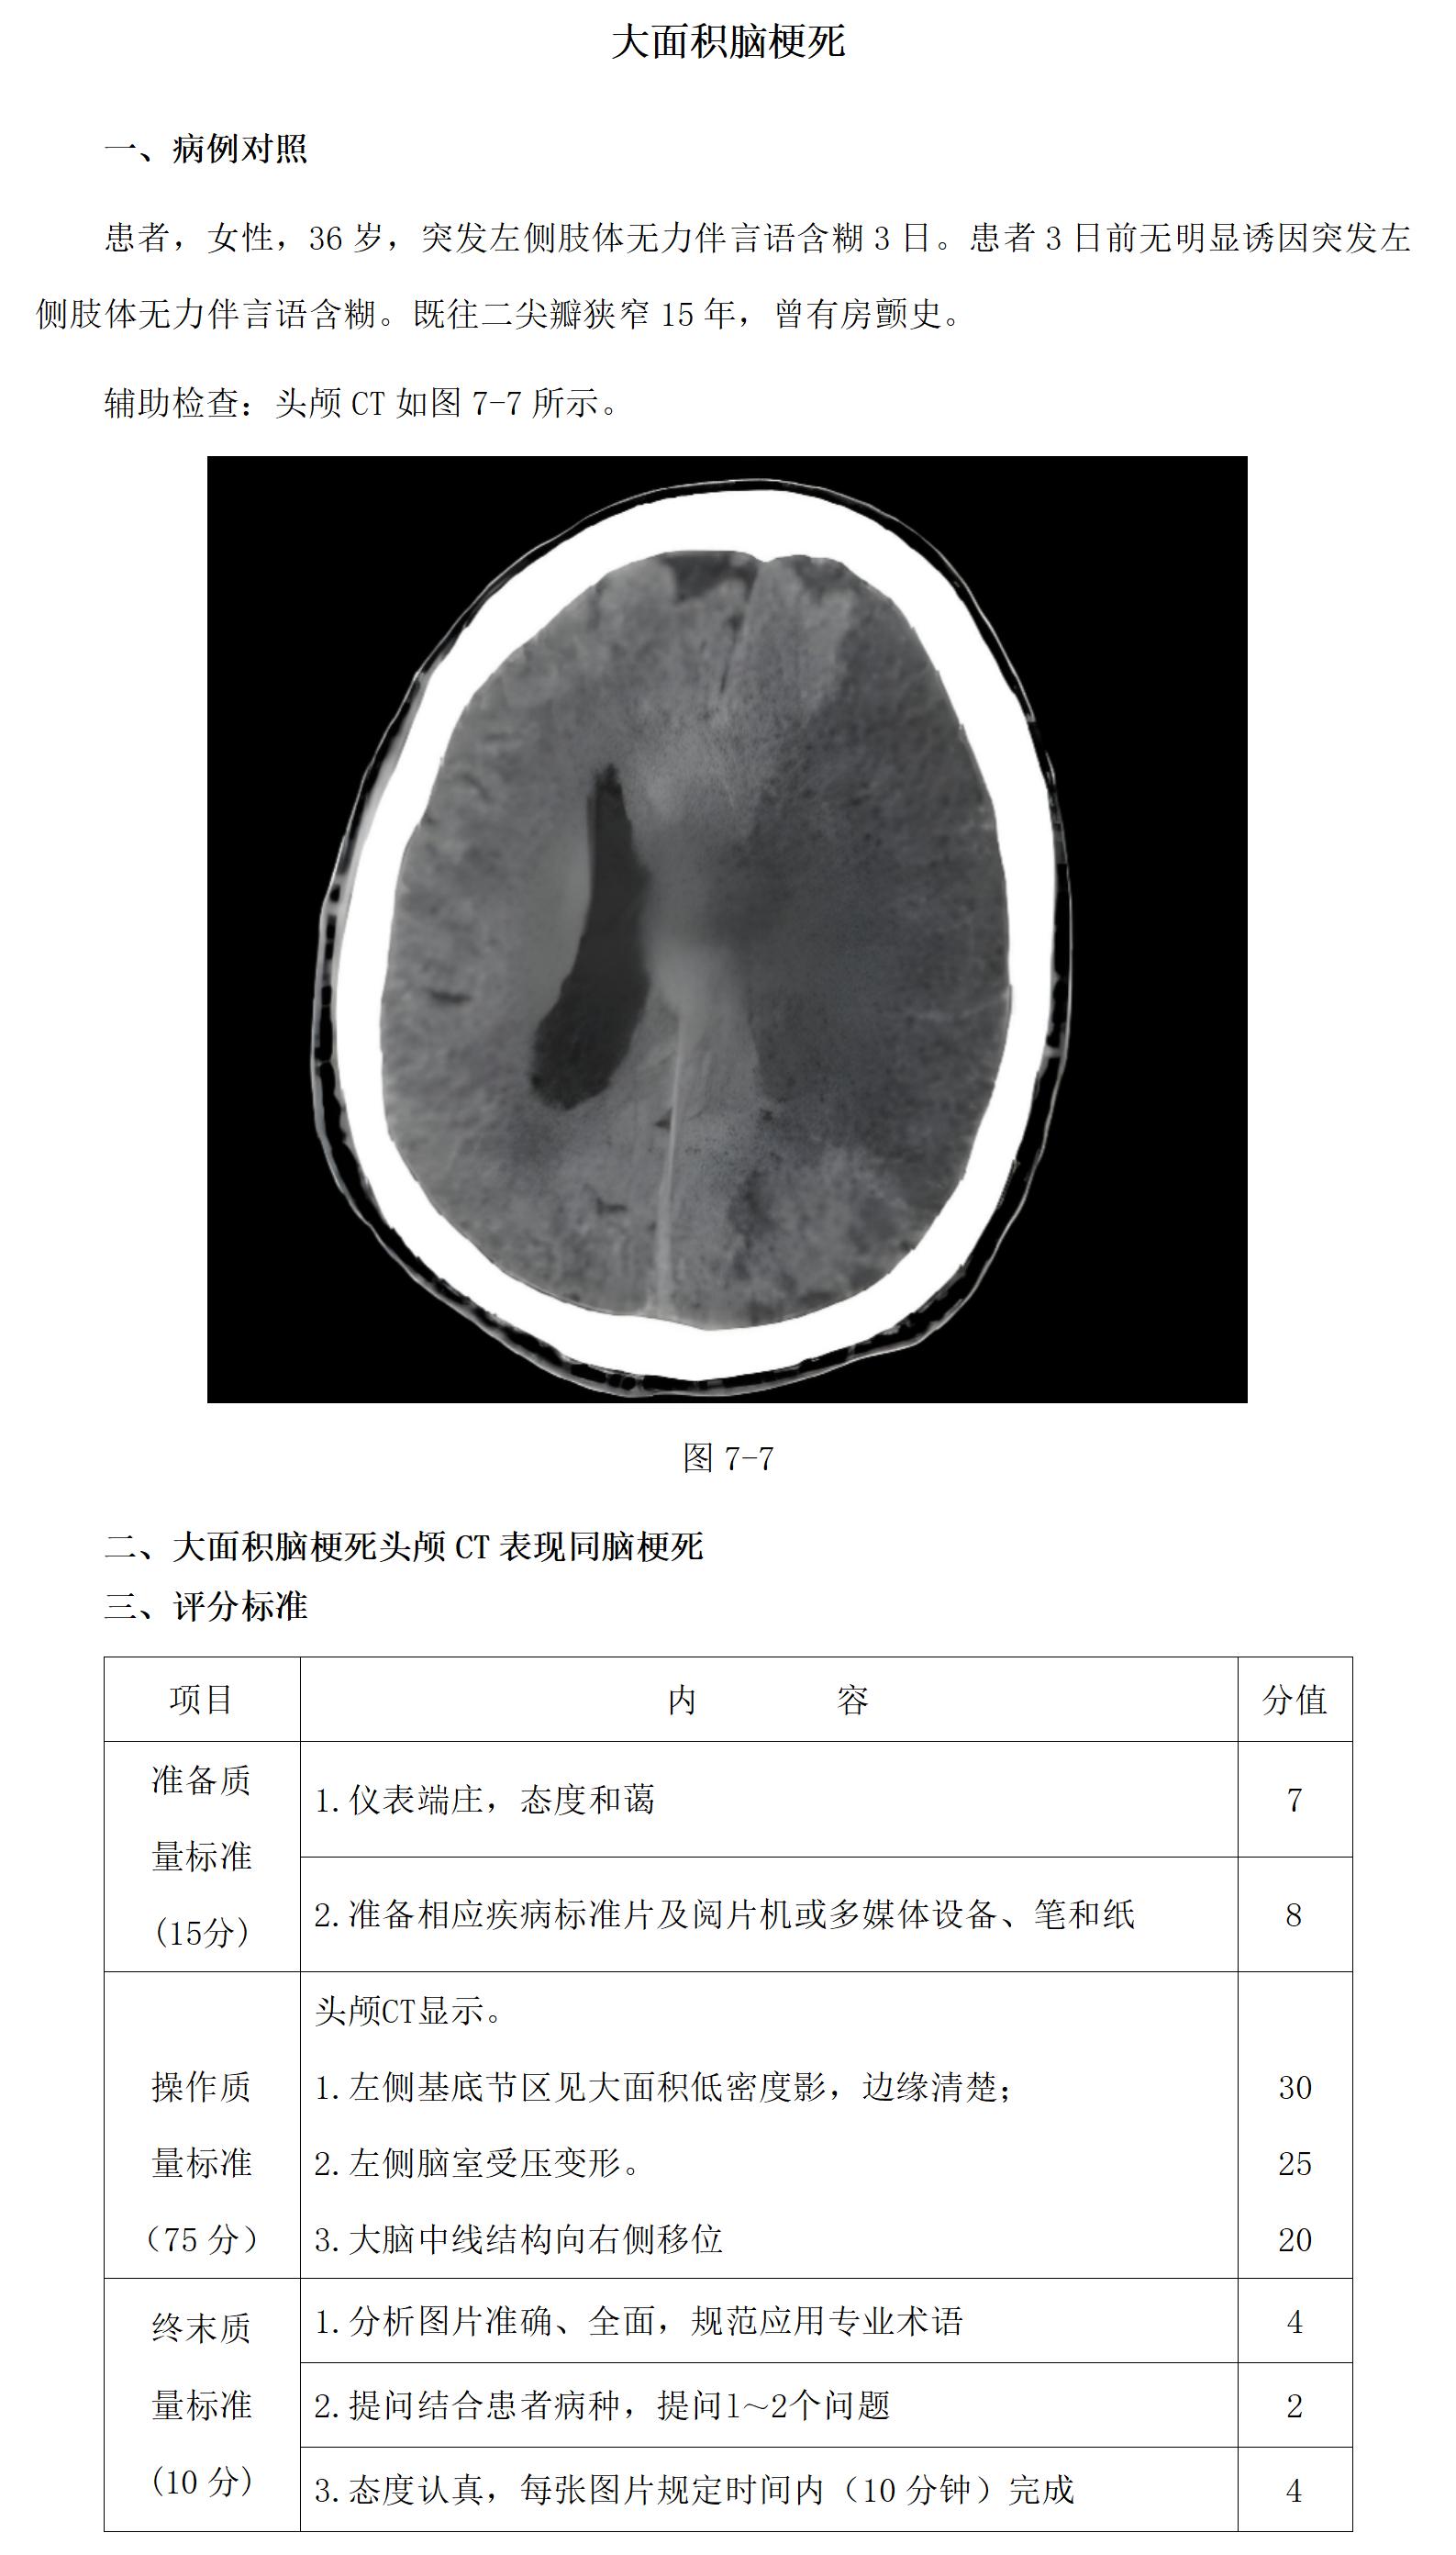

18-2 大面积脑梗死